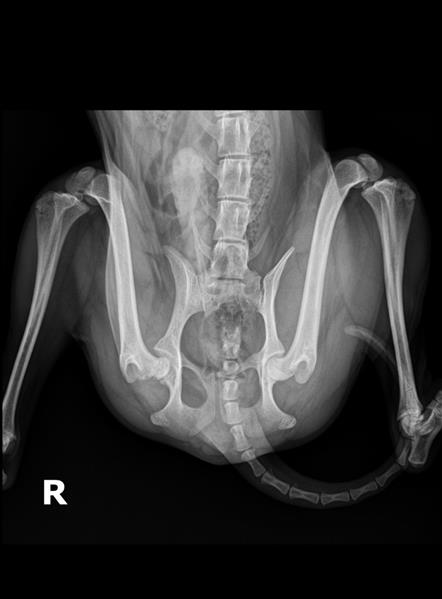

정확한 것은 임상증상도 확인하고, 촉진검사 등이 함께 필요하지만, 우선 올려주신 엑스레이 사진으로만 봤을 때 RT후지 대퇴골두 이형성 소견이 보입니다. 대퇴골두 제거수술이 필요할 것으로 보입니다.